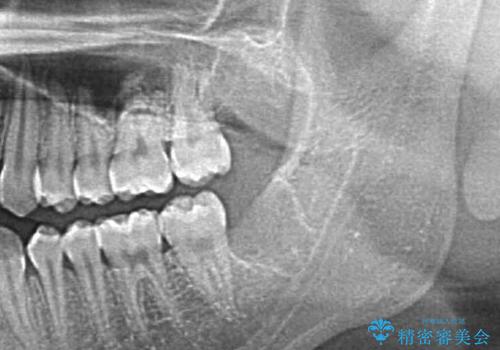

- 親知らずの抜歯希望で来院されました。

左側の親知らずを上下同時に抜いていきます。

時間は約60分で施術しました。

親知らずは入院せずとも通院で片側上下同時に抜くことが可能です。

手前の歯の虫歯リスクを下げるためにも、骨から出てきた親知らずは抜くことをお勧めします。

また術後丁寧に縫合をすることで治癒後の歯茎の状態もきれいにすることができます。